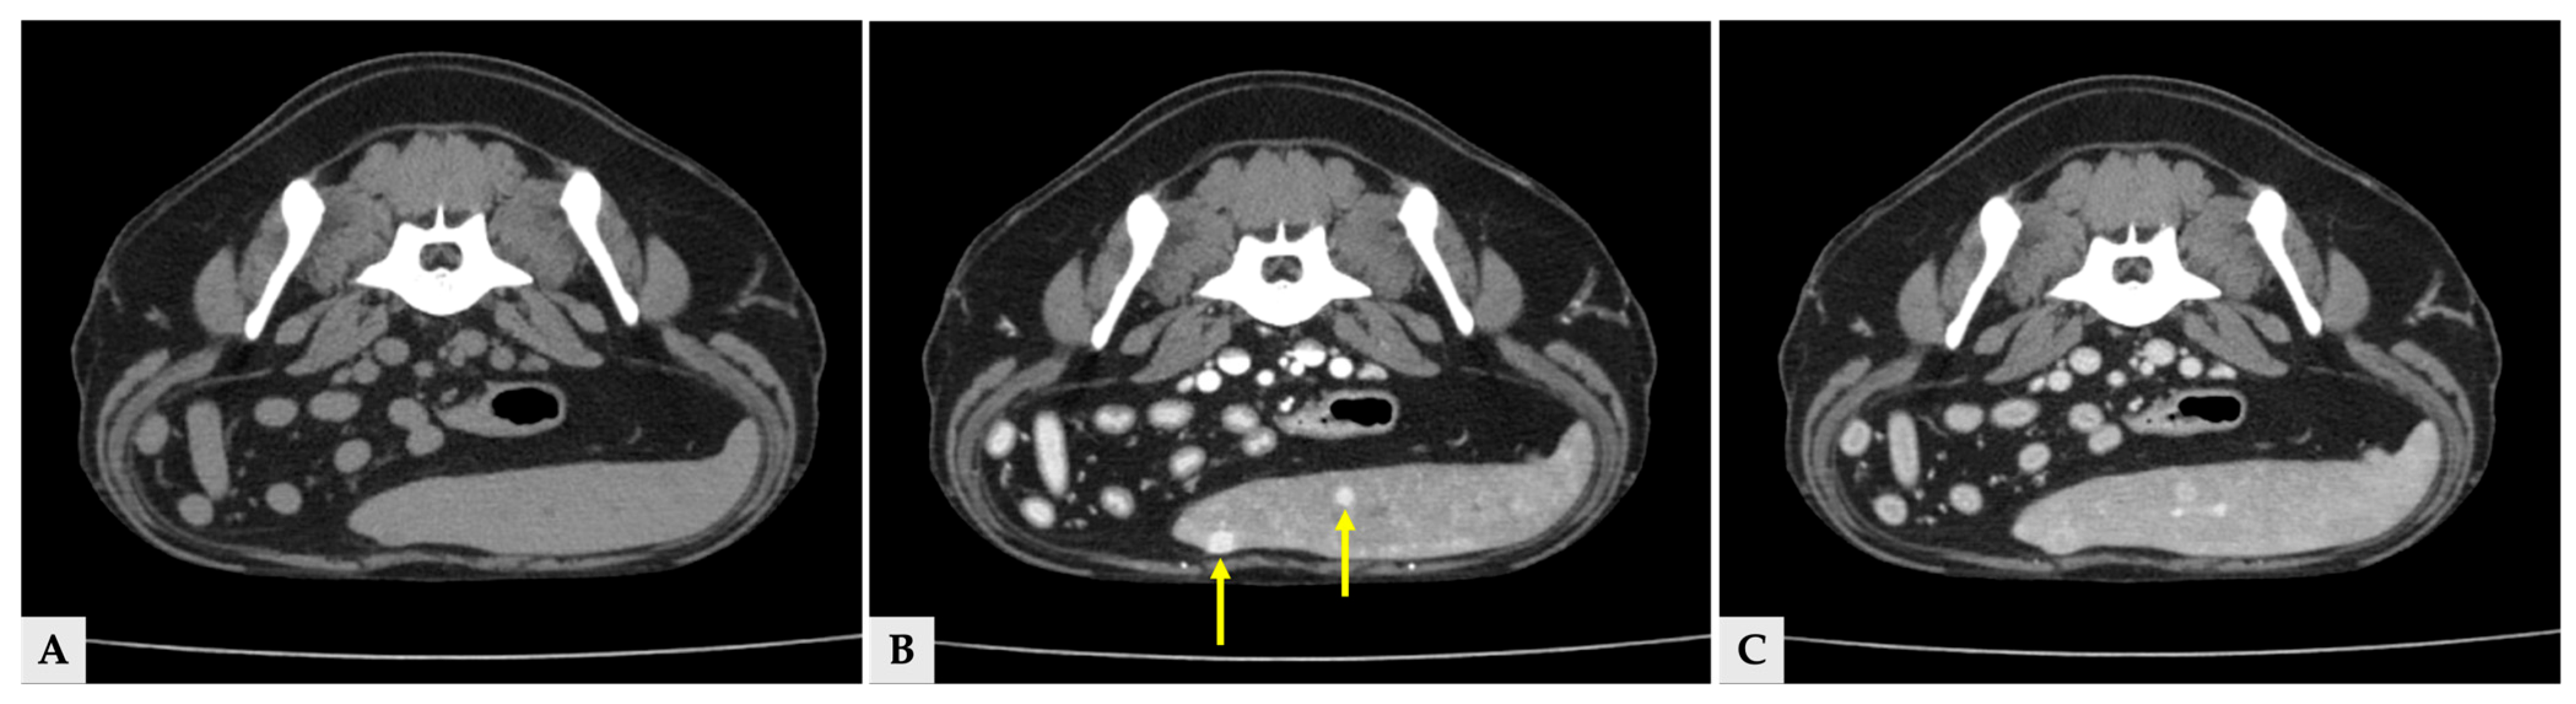

Multiple hyper- and hypoattenuating hepatic nodules were scattered throughout the liver parenchyma (maximum size 11.4 mm × 11.9 mm × 10.8 mm) (Figure 3), and numerous small splenic nodules exhibiting on pre-contrast and portal phase were also observed (Figure 4). Additionally, a soft-tissue mass was detected at the esophagogastric junction. Cervical ultrasonography revealed three distinct, heterogeneous right thyroid masses, with the largest mass demonstrating prominent vascularity on Doppler evaluation (Figure 5).

Figure 3.

Transverse view of the CT images of several hepatic nodules at the same anatomical level. (A) Pre-contrast image showing a liver nodule with attenuation similar to the surrounding hepatic parenchyma. (B) Portal phase image at the same level demonstrating heterogeneous hyperattenuation (arrow) and hypoattenuation (arrowhead). (C) Delayed phase image at the corresponding level, in which the nodules show attenuation similar to the surrounding hepatic parenchyma. The yellow arrows in all three images indicate the same liver nodule (11.4 mm × 11.9 mm × 10.8 mm).

Figure 4.

Transverse CT images of splenic nodules at the same anatomical level. (A) Pre-contrast image showing splenic nodules that are isoattenuated relative to the surrounding splenic parenchyma. (B) Portal phase image at the same level demonstrating hyperattenuated splenic nodules (arrows). (C) Delayed phase image at the corresponding level, in which the splenic nodules show attenuation similar to or slightly higher than the surrounding splenic parenchyma.